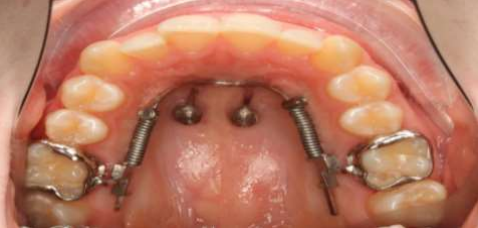

2 - Be realistic about planned movements. Use non-compliance aids such as partial arches and TADs to achieve predictable movements (see Fig. 1-3). Perform pre-treatments and shorten treatment time with aligners. No one wants to wear over 100 aligners.

Fig. 4: Example of a hybrid treatment: Aligner therapy with a Bene slider for distalization to avoid an unnecessary number of aligners. The patient wears the aligners up to the maxillary premolars (tooth 25, 35).